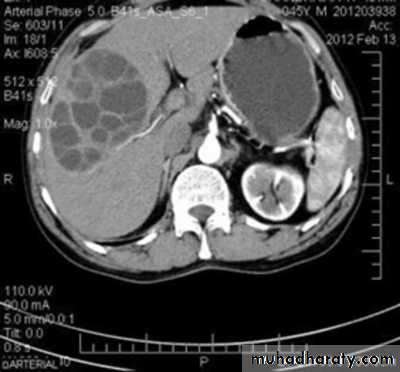

Pancreatitis

Patient present with abdominal pain , vomiting with or without jaundice , increase amylase levelCT finding

Enlargement of the pancreas focal or generalized increase in size .

Hypo density within the pancreas focal or generalized due to the edema .

Peri pancreatic fluid collection & edema around the pancreas .

The fluid around the pancreas if persist more than 6 w become encysted leading to the pancreatic pseudo cyst any area could be affected .

Edema of the wall of the stomach .